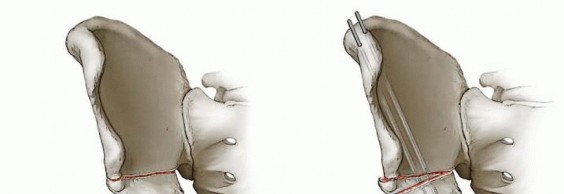

هنا يأتي دور "جراحة الحوض المحافظة"، والتي تهدف بشكل أساسي إلى الحفاظ على المفصل الطبيعي وإعادة بناء التشريح الطبيعي للورك، وتحسين توافق المفصل، وإعادة توزيع الضغوط على السطح المفصلي، وبالتالي إبطاء تقدم المرض التنكسي. جراحة تقويم الحوض حول الحُق (Periacetabular Osteotomy - PAO)، التي وصفها البروفيسور غانز لأول مرة، أصبحت المعيار الذهبي لإعادة توجيه التجويف الحُقي لدى المراهقين والشباب البالغين الذين يعانون من خلل التنسج الوركي المصحوب بأعراض، وقد أظهرت نتائج ممتازة على المدى الطويل في الحفاظ على وظيفة الورك الطبيعية.

تُعد جراحة تقويم الحوض حول الحُق (PAO)، والتي طوّرها البروفيسور غانز، هي الأسلوب الجراحي الأكثر شيوعاً وفعالية لتحقيق هذه الأهداف في المرضى البالغين والمراهقين بعد اكتمال نمو الهيكل العظمي.

تقويم الحوض حول الحُق (Periacetabular Osteotomy - PAO): تُعد هذه الجراحة المعيار الذهبي لإعادة توجيه التجويف الحُقي لدى المراهقين والشباب البالغين الذين يعانون من خلل التنسج الوركي المصحوب بأعراض. تتضمن قطعاً دقيقة حول التجويف الحُقي لتحرير جزء من عظم الحوض الذي يحتوي على التجويف، ثم إعادة توجيهه إلى وضعية أفضل لتغطية رأس الفخذ بشكل كامل، ثم تثبيته في مكانه الجديد بالمسامير. تتميز هذه الجراحة بالحفاظ على سلامة الحلقة الحوضية الخلفية، مما يسمح بالتحميل المبكر على الساق بعد الجراحة في بعض البروتوكولات.